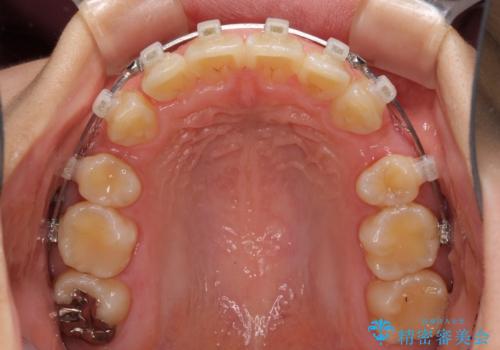

- クリアブラケット

- 上下前歯を部分矯正したところ出っ歯になってしまったとのことで来院された患者様です。

上下左右第一小臼歯4本を抜歯して、積極的に口元を引っ込めるよう、ワイヤー装置にて矯正治療を行うこととしました。